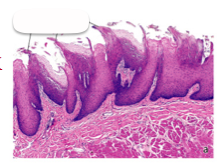

Name this tissue

Filiform papillae of specialized oral mucosa